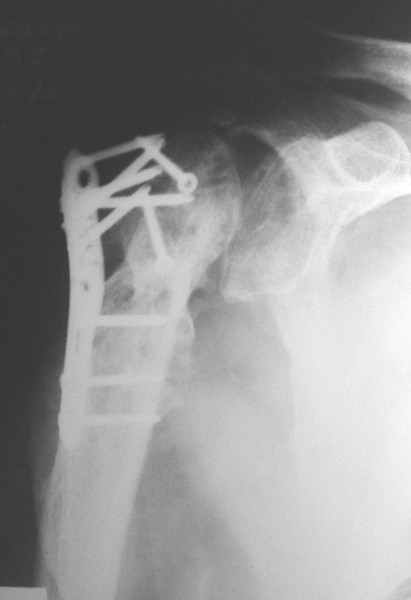

Уважаемые коллеги, каково ваше мнение по поводу необходимости удаления металлоконструкций в данном случае - мужчина, 53 лет, сопутстувующая патология - схараный диабет 2 типа, впервые выявленный, ГБ 1-2 ст., хр.калькулезный холецистит, хр.гепатит. Операция произведена в январе 2009 г. через 18 сут. после получения травмы.